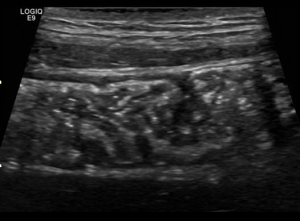

Gastrointestinal Sonography